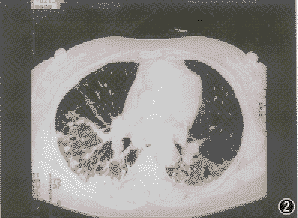

非特異性間質性肺炎影像學特點:高分辨CT顯示雙肺對稱性毛玻璃影或雙肺肺泡腔的實變影。

電子顯微鏡鏡下肺炎支原體三、咳嗽以夜間為重,偶爾有少量黃粘痰,入院前1個月出現活動後氣短,漸加重至上一層樓梯亦有症狀,同時伴胸背持續鈍痛。病程中有間斷髮熱,無關節肌肉痛史。體格檢查:輕度紫紺,無杵狀指,雙肺可聞爆裂音。血ANA、抗ds-DNA、RF及抗ENA均陰性。胸片示雙中下肺間質紋理厚,呈磨玻璃樣改變伴小斑片結節狀影。HRCT(圖4)見右肺中葉、左肺舌葉及雙肺下葉密度增高呈磨玻璃樣改變,雙肺支氣管血管紋理增厚,右肺中葉內側段支氣管擴張,雙側胸膜不規則增厚,縱隔內及雙肺門淋巴結多發鈣化。血氣分析PaO261.4mmHg。BALF細胞總數1.27×109/L,淋巴細胞占32%,中性細胞占47%,巨噬細胞占21%;T淋巴細胞亞群分析:CD417.6%,CD877.7%,CD4∶CD8=0.227。經支氣管肺活檢(TBLB)病理所見為少許血管及破碎的支氣管黏膜上皮呈急性及慢性炎。經電視引導下胸腔鏡肺活檢確診為非特異性間質性肺炎。

2.HRCT的主要特徵是:雙側、對稱、主要在下肺的網狀陰影,伴牽拉性支氣管擴張和下葉體積減少,通常為瀰漫性或胸膜下分布,但有時病變並不累及胸膜下肺組織。